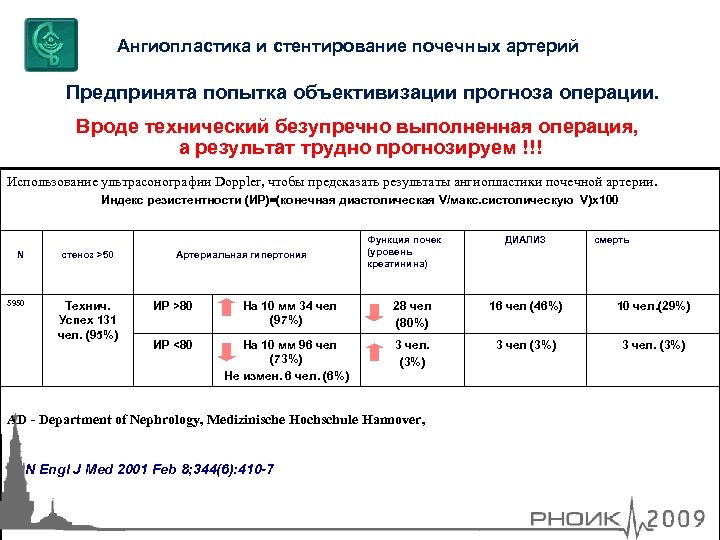

Ангиопластика и стентирование почечных артерий Предпринята попытка объективизации прогноза операции. Вроде технический безупречно выполненная операция, а результат трудно прогнозируем !!! Использование ультрасонографии Doppler, чтобы предсказать результаты ангиопластики почечной артерии. Индекс резистентности (ИР)=(конечная диастолическая V/макс. систолическую V)х100 N 5950 стеноз >50 Технич. Успех 131 чел. (95%) Артериальная гипертония Функция почек (уровень креатинина) ДИАЛИЗ смерть ИР >80 На 10 мм 34 чел (97%) 28 чел (80%) 16 чел (46%) 10 чел. (29%) ИР <80 На 10 мм 96 чел (73%) Не измен. 6 чел. (6%) 3 чел. (3%) AD - Department of Nephrology, Medizinische Hochschule Hannover, N Engl J Med 2001 Feb 8; 344(6): 410 -7

Ангиопластика и стентирование почечных артерий Предпринята попытка объективизации прогноза операции. Вроде технический безупречно выполненная операция, а результат трудно прогнозируем !!! Использование ультрасонографии Doppler, чтобы предсказать результаты ангиопластики почечной артерии. Индекс резистентности (ИР)=(конечная диастолическая V/макс. систолическую V)х100 N 5950 стеноз >50 Технич. Успех 131 чел. (95%) Артериальная гипертония Функция почек (уровень креатинина) ДИАЛИЗ смерть ИР >80 На 10 мм 34 чел (97%) 28 чел (80%) 16 чел (46%) 10 чел. (29%) ИР <80 На 10 мм 96 чел (73%) Не измен. 6 чел. (6%) 3 чел. (3%) AD - Department of Nephrology, Medizinische Hochschule Hannover, N Engl J Med 2001 Feb 8; 344(6): 410 -7